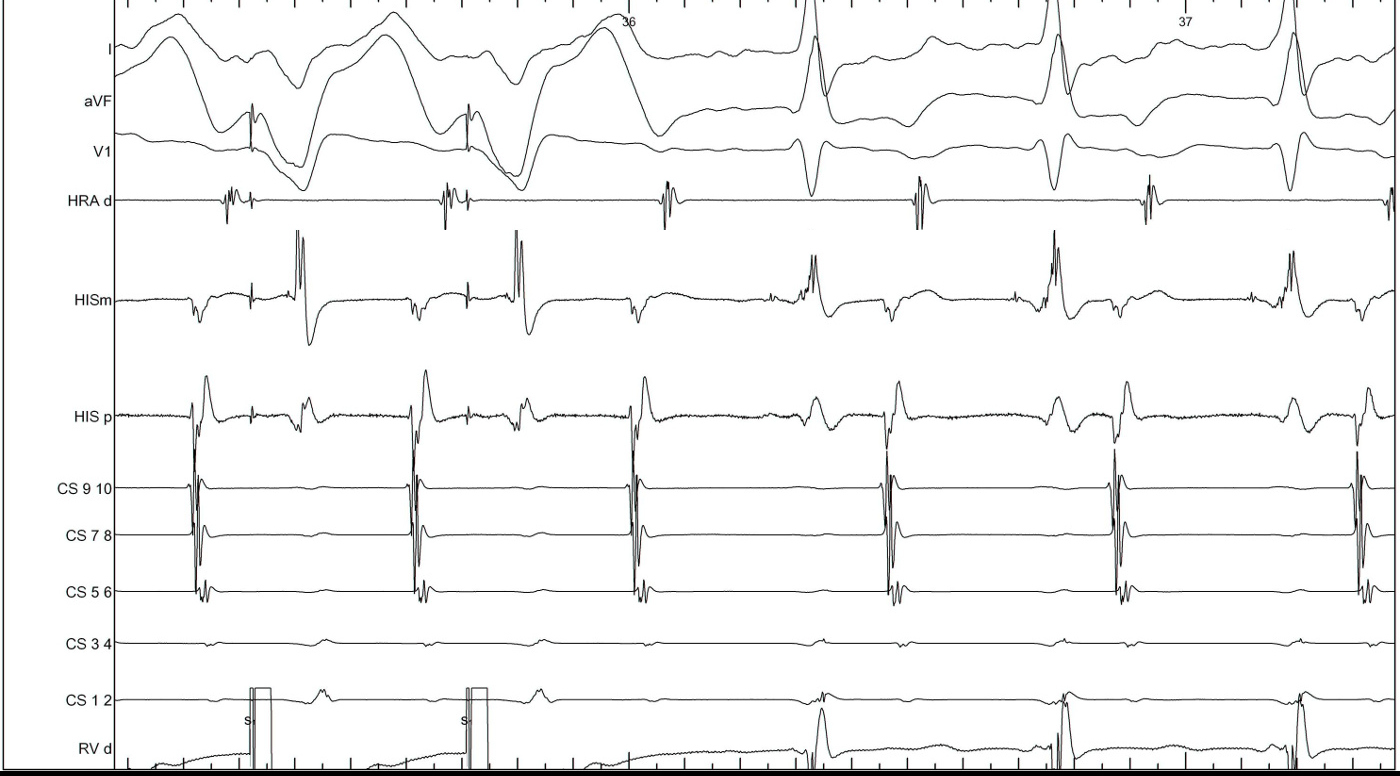

RV pacing in narrow QRS tachycardia - AVNRT / AVRT

vav_measurements_ppi.jpg

SA / VA intervals

sa_va.jpg